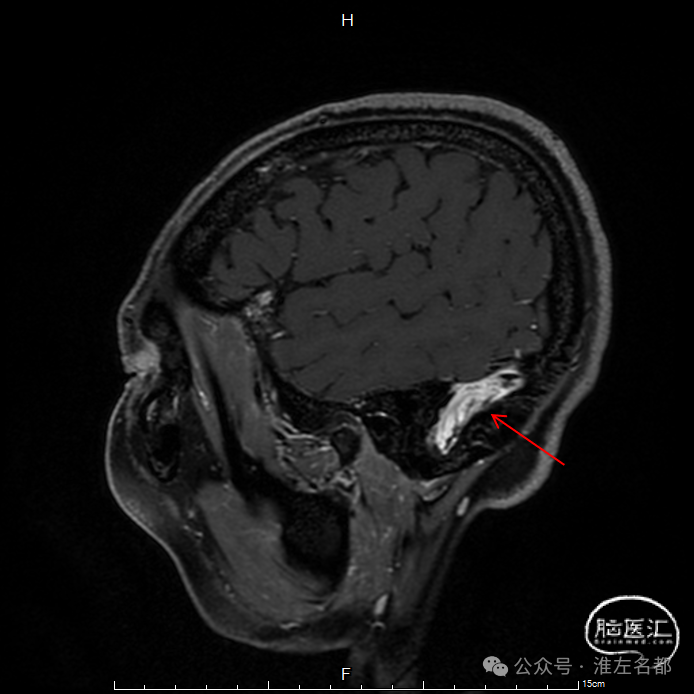

三维黑血高分辨T1

三维黑血高分辨T1平扫(上图)和增强(下图):右侧乙状窦慢性血栓,平扫呈等低信号,并显著强化。

三维黑血高分辨T1平扫(上图)和增强(下图):左侧乙状窦局部未发育。